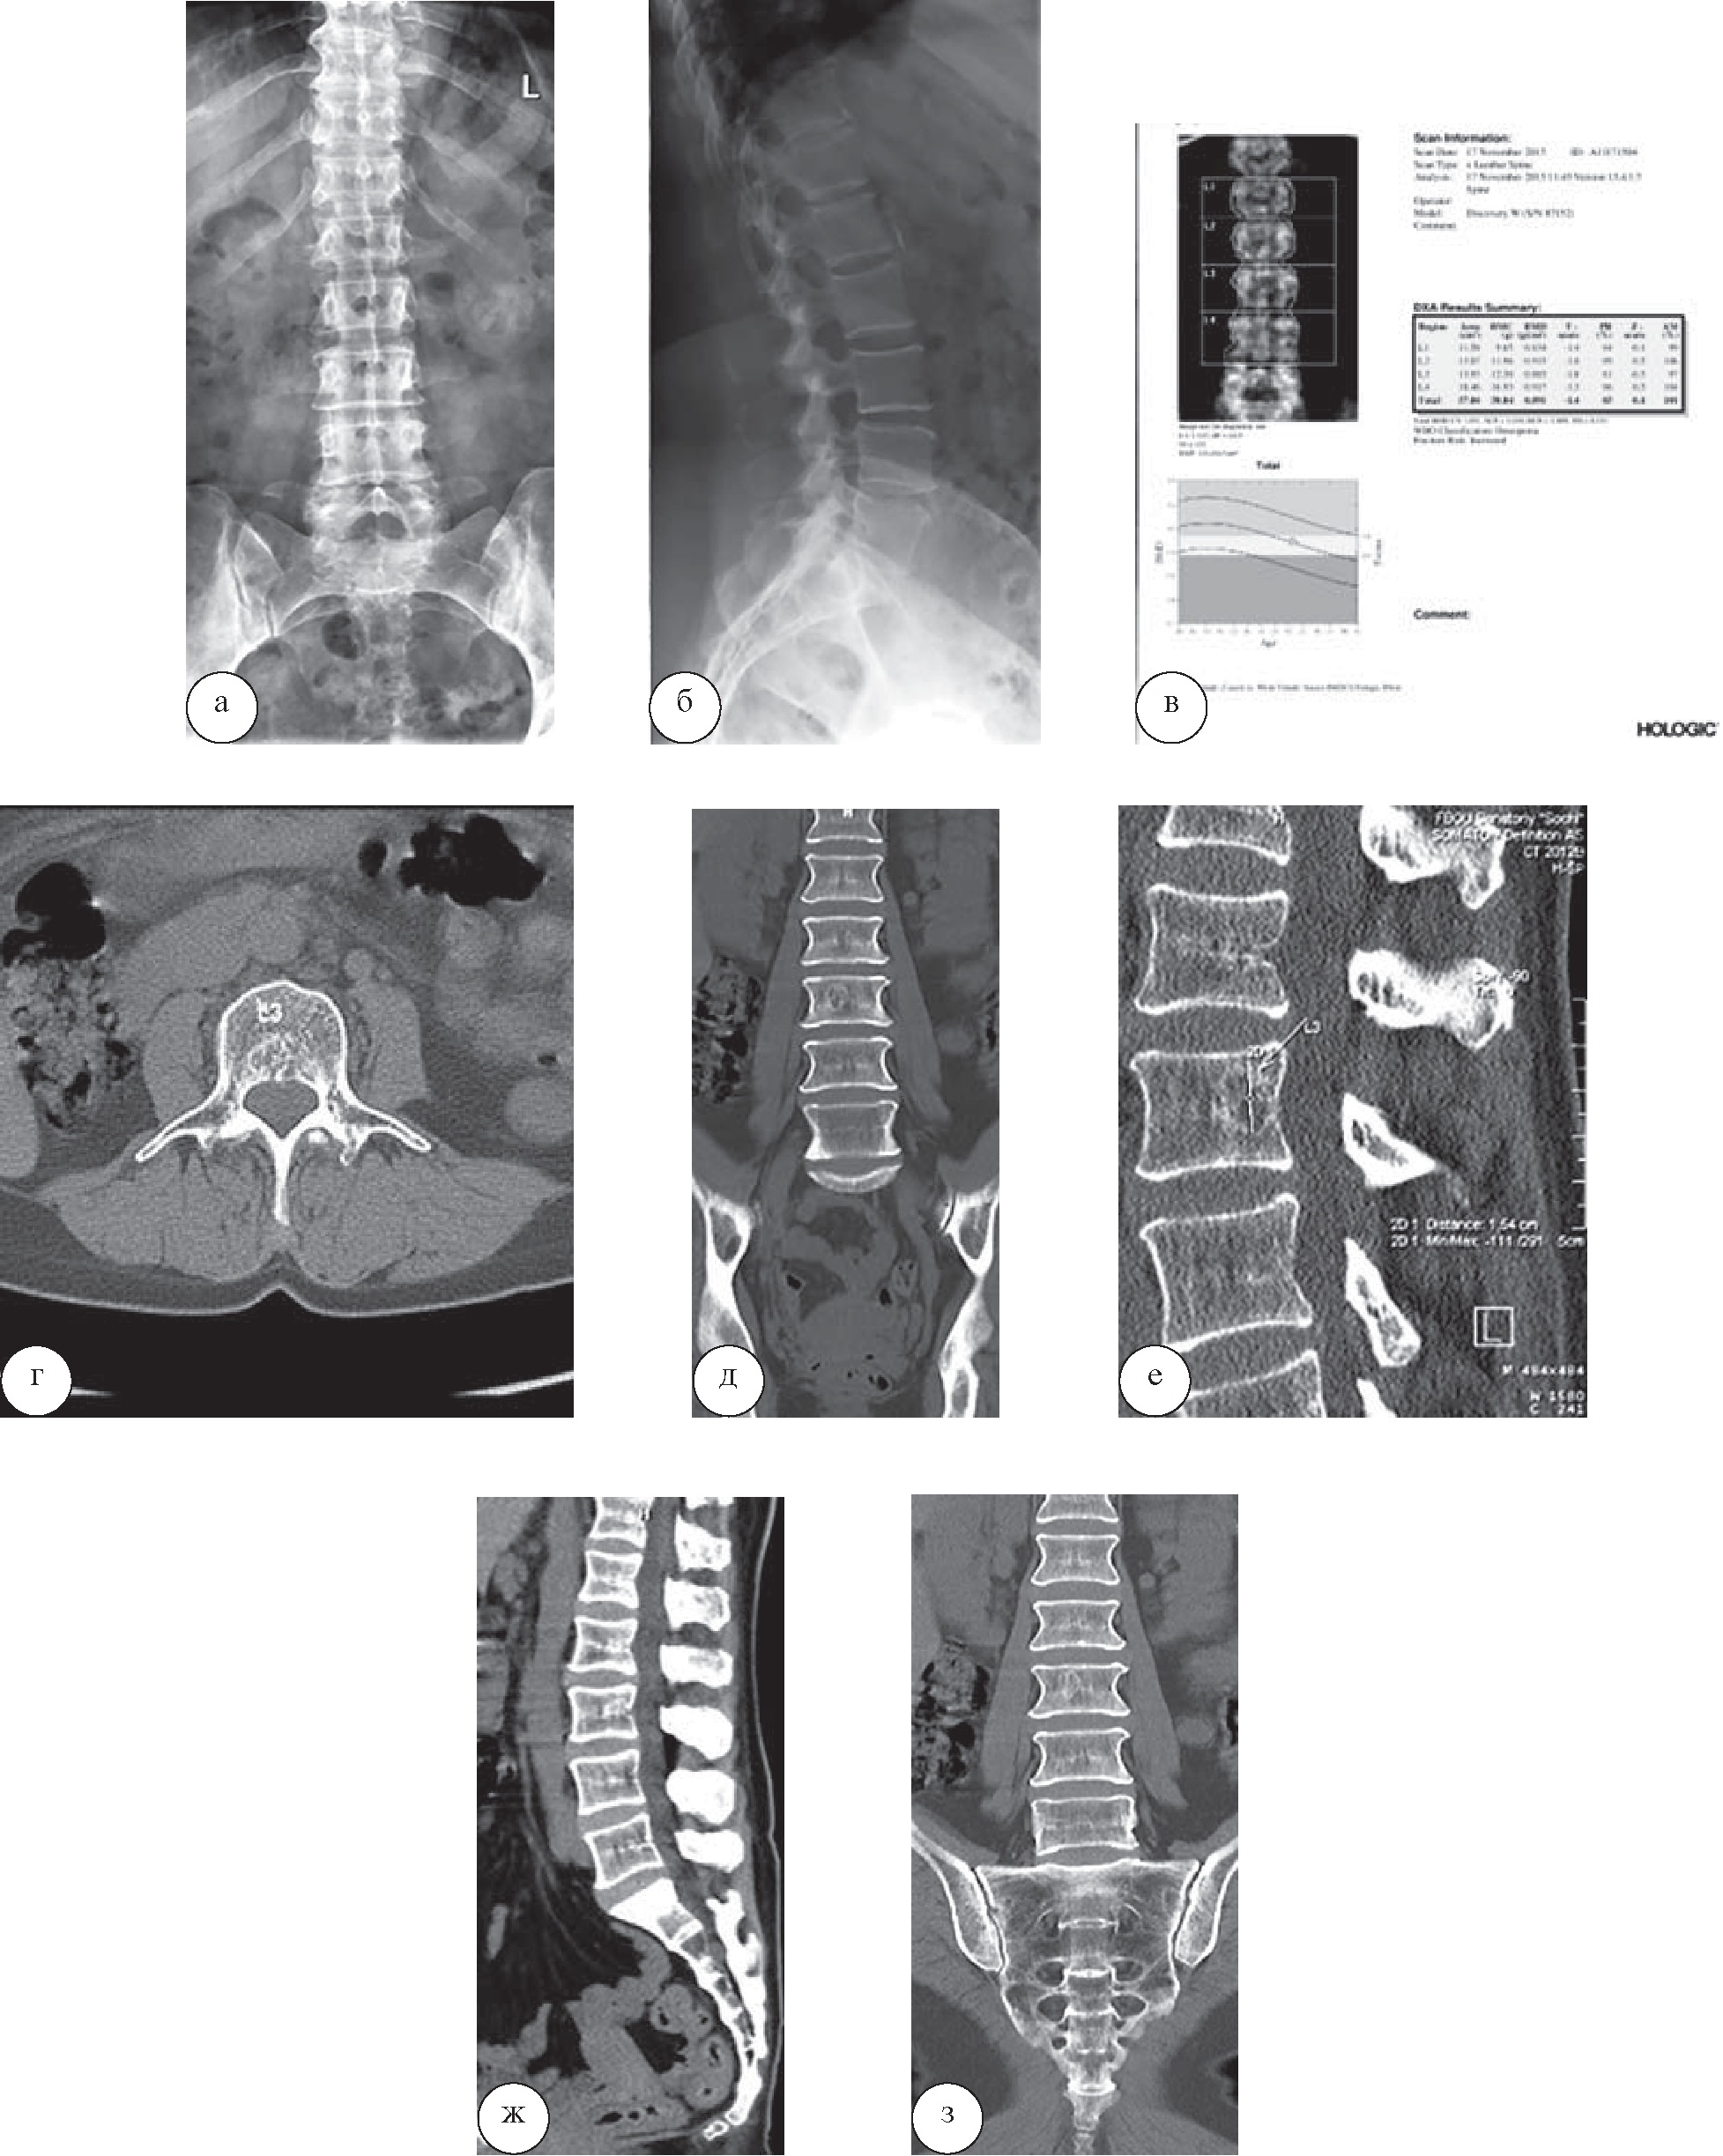

У пациентки 44 лет, прибывшей на лечение по поводу остеохондроза, в санатории выполнена КТ, позволившая диагностировать спондилолистез I степени и протрузий размерами менее 3 мм (рис. 1). В санаторной карте пациентки имелись лишь общие сведения. Данные рентгенологического обследования свидетельствовали о наличии остеохондроза, при этом спондилолистез диагностирован не был. КТ была выполнена с целью оценки изменений межпозвоночных дисков. Однако выявленные изменения не препятствовали возможности установления интенсивного режима функциональных нагрузок; противопоказаний, препятствующих назначению каких-либо методик лечебного воздействия, также не выявлено.

Рис. 1. Пациентка Т., 44 года. На КТ поясничного отдела позвоночника в аксиальной (а, б) и сагиттальной плоскостях (в, г) определяются остеохондроз поясничного отдела позвоночника I степени, протрузии межпозвонковых дисков L4–5 и L5–S1, не превышающие 3 мм, спондилоартроз, передний дегенеративный спондилолистез позвонка L3 I степени (менее 1/4 ширины позвонка) без признаков дегенеративного сужения позвоночного канала и выраженной нестабильности